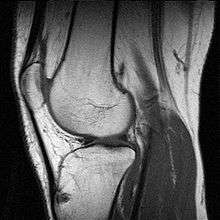

MRI uses strong magnetic fields to align atomic nuclei (usually hydrogen protons) within body tissues, then uses a radio signal to disturb the axis of rotation of these nuclei and observes the radio frequency signal generated as the nuclei return to their baseline states.[4] The radio signals are collected by small antennae, called coils, placed near the area of interest. An advantage of MRI is its ability to produce images in axial, coronal, sagittal and multiple oblique planes with equal ease. MRI scans give the best soft tissue contrast of all the imaging modalities. With advances in scanning speed and spatial resolution, and improvements in computer 3D algorithms and hardware, MRI has become an important tool in musculoskeletal radiology and neuroradiology.

One disadvantage is the patient has to hold still for long periods of time in a noisy, cramped space while the imaging is performed. Claustrophobia severe enough to terminate the MRI exam is reported in up to 5% of patients. Recent improvements in magnet design including stronger magnetic fields (3 teslas), shortening exam times, wider, shorter magnet bores and more open magnet designs, have brought some relief for claustrophobic patients. However, for magnets with equivalent field strengths, there is often a trade-off between image quality and open design. MRI has great benefit in imaging the brain, spine, and musculoskeletal system. The use of MRI is currently contraindicated for patients with pacemakers, cochlear implants, some indwelling medication pumps, certain types of cerebral aneurysm clips, metal fragments in the eyes and some metallic hardware due to the powerful magnetic fields and strong fluctuating radio signals to which the body is exposed. Areas of potential advancement include functional imaging, cardiovascular MRI, and MRI-guided therapy.